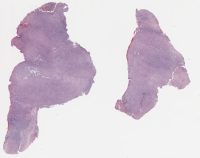

CANP2008-5.svs

12000 x 17372

@ 20X